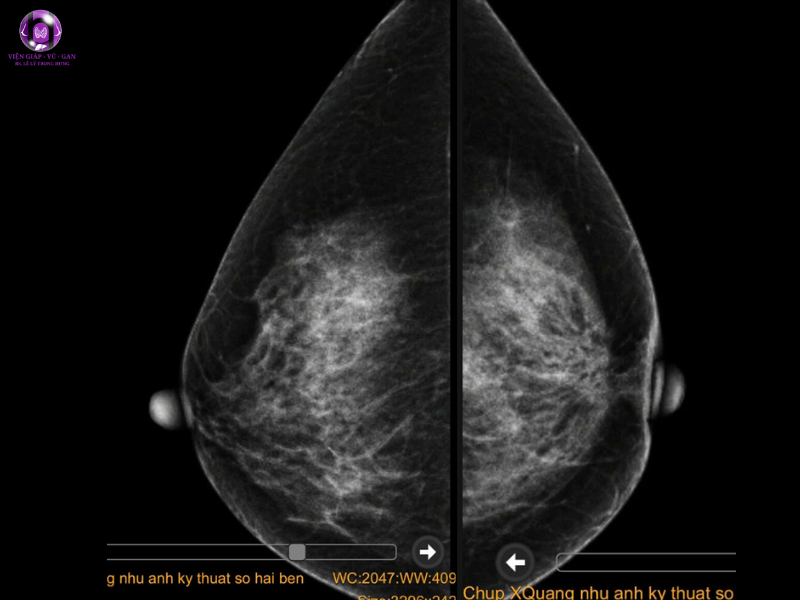

- Tham khảo kết quả nhũ ảnh của BV:

- Sau núm vú trái có vùng xáo trộn cấu trúc 29x45mm ( BIRADS 4)